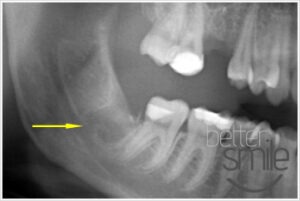

- Stan po miesiącu od zabiegu, ząb został usunięty, gojenie przebiega prawidłowo.